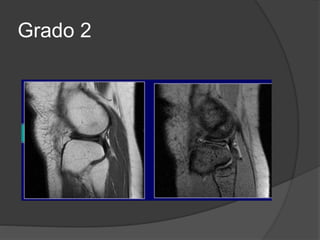

Grado 2

Grado II

• Roturas parciales

• Ligamento engrosado y áreas de hiperseñal en T1 y T2.

• Las fibras ligamentosas están separadas del hueso

cortical debido a la presencia de edema y hemorragia.